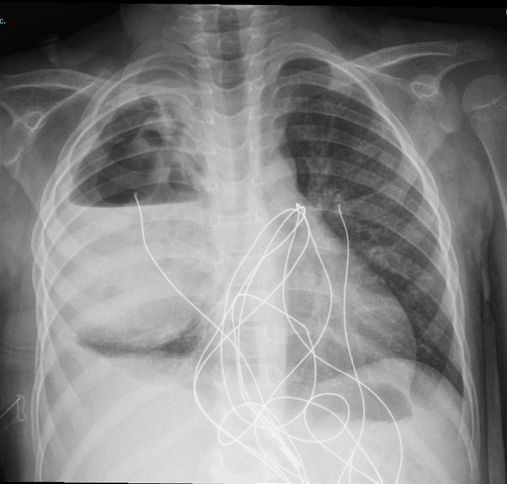

Since admission, the patient continued to experience intermittent fever. Chest radiography on day six (Figure 1) and thoracic computed tomography (CT) scan on day eight (Figure 2) are shown below.

Figure 1. Chest radiograph showing a large round hypotransparency occupying almost the entire right hemithorax, and a hypotransparency in the lower third of the right pulmonary field, associated with blunting of the ipsilateral costophrenic angle.